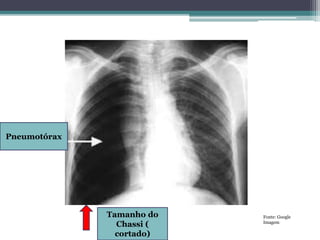

Pneumotórax

Tamanho do

Chassi (

cortado)

Fonte: Google

Imagem